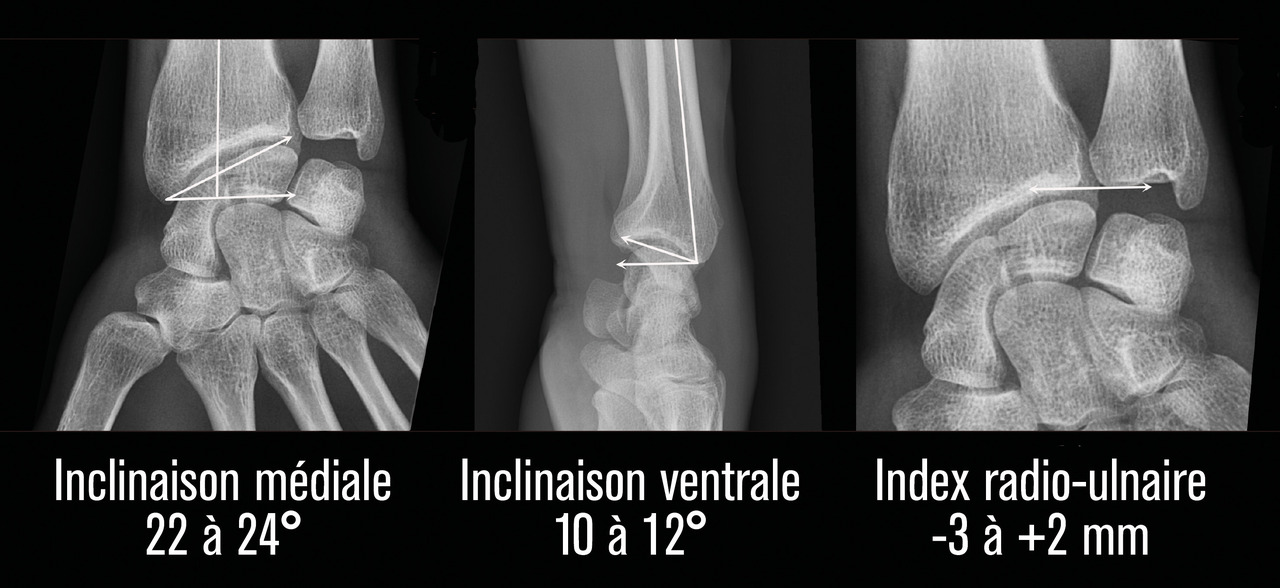

La surface articulaire distale, encroûtée de cartilage, répond au carpe distalement et présente deux facettes, scaphoïdienne et lunarienne (fig. 3), séparées par une crête de direction antéropostérieure. Cette surface articulaire a une double concavité transversale et sagittale. Il est crucial de retenir qu’elle possède une double inclinaison ventrale (10 à 12° en moyenne dans le plan sagittal) et médiale (22 à 24° en moyenne dans le plan coronal), très spécifique, qu’il faudra s’efforcer de restituer et de maintenir dans le traitement de la composante métaphysaire de ces fractures (fig. 4). L’index radio-ulnaire distal, défini par la longueur relative du radius par rapport à l’ulna, est le troisième critère morphologique à évaluer (fig. 4). Ce dernier, dont les valeurs normales sont très variables, est en moyenne neutre à 0 mm (-3 mm à +2 mm).